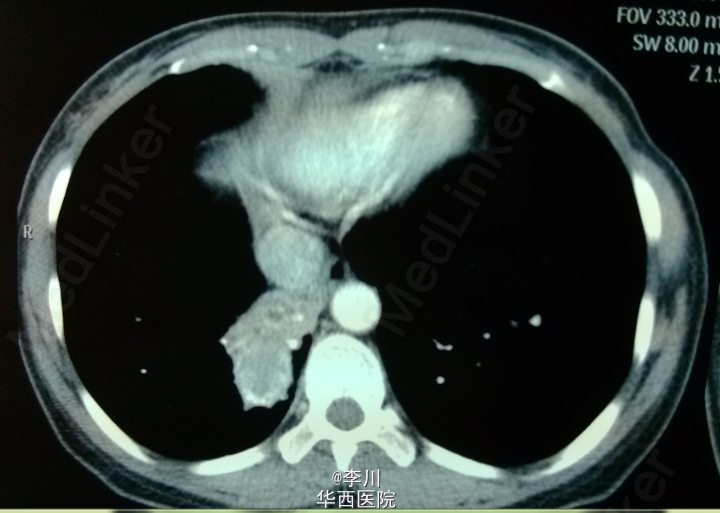

患者为43岁女性,因“咳嗽咳痰伴胸闷、气紧4+月”入院。患者4+月前无明显诱因出现咳嗽咳痰,伴胸闷气紧,外院行相关检查后诊断为“肺炎”,予抗感染治疗20天后无明显缓解。遂于我院就诊。

查体:双侧锁骨上淋巴结未触及肿大。视:双侧胸廓对称,未见畸形,双肺呼吸动度对称。触:触觉语颤对称,未触及胸膜摩擦感,心尖搏动位于左锁骨中线,未见异常搏动。叩:双肺叩清音,双肺活动度对称。听:右下肺肺呼吸音低,未闻及干湿罗音及胸膜摩擦音,心前区未及病理性杂音。我院胸部CT示:右肺下叶不规则片团影,伴右肺下叶不张。

术前诊断为右下肺结核球。于全麻下行右肺下叶切除术。术中取出病灶,可见干酪样坏死。术后病理确诊为肺结核病灶。术后患者恢复可,仍需抗痨治疗。